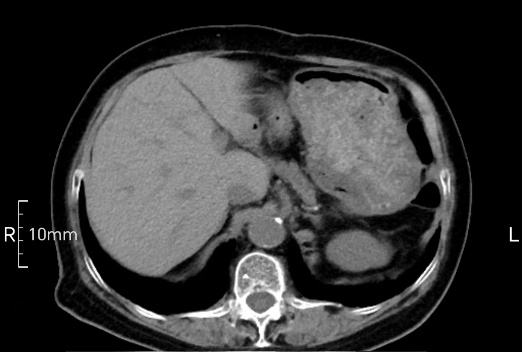

看看下面三幅便知遵醫(yī)囑的重要性。

禁食但檢查前沒有喝飽,胃未能漲開,胃壁觀察效果不佳。